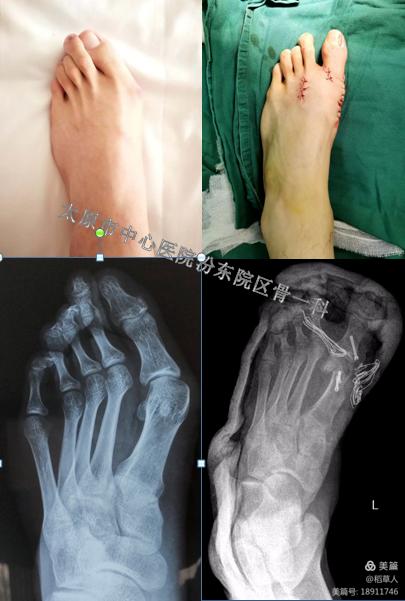

这是一名19岁的男孩,虽然年纪很小,但是踇外翻已经已经很严重并且累及临近的足趾,出现了爪状趾畸形,于是需要附加做松解及术后的石膏固定。